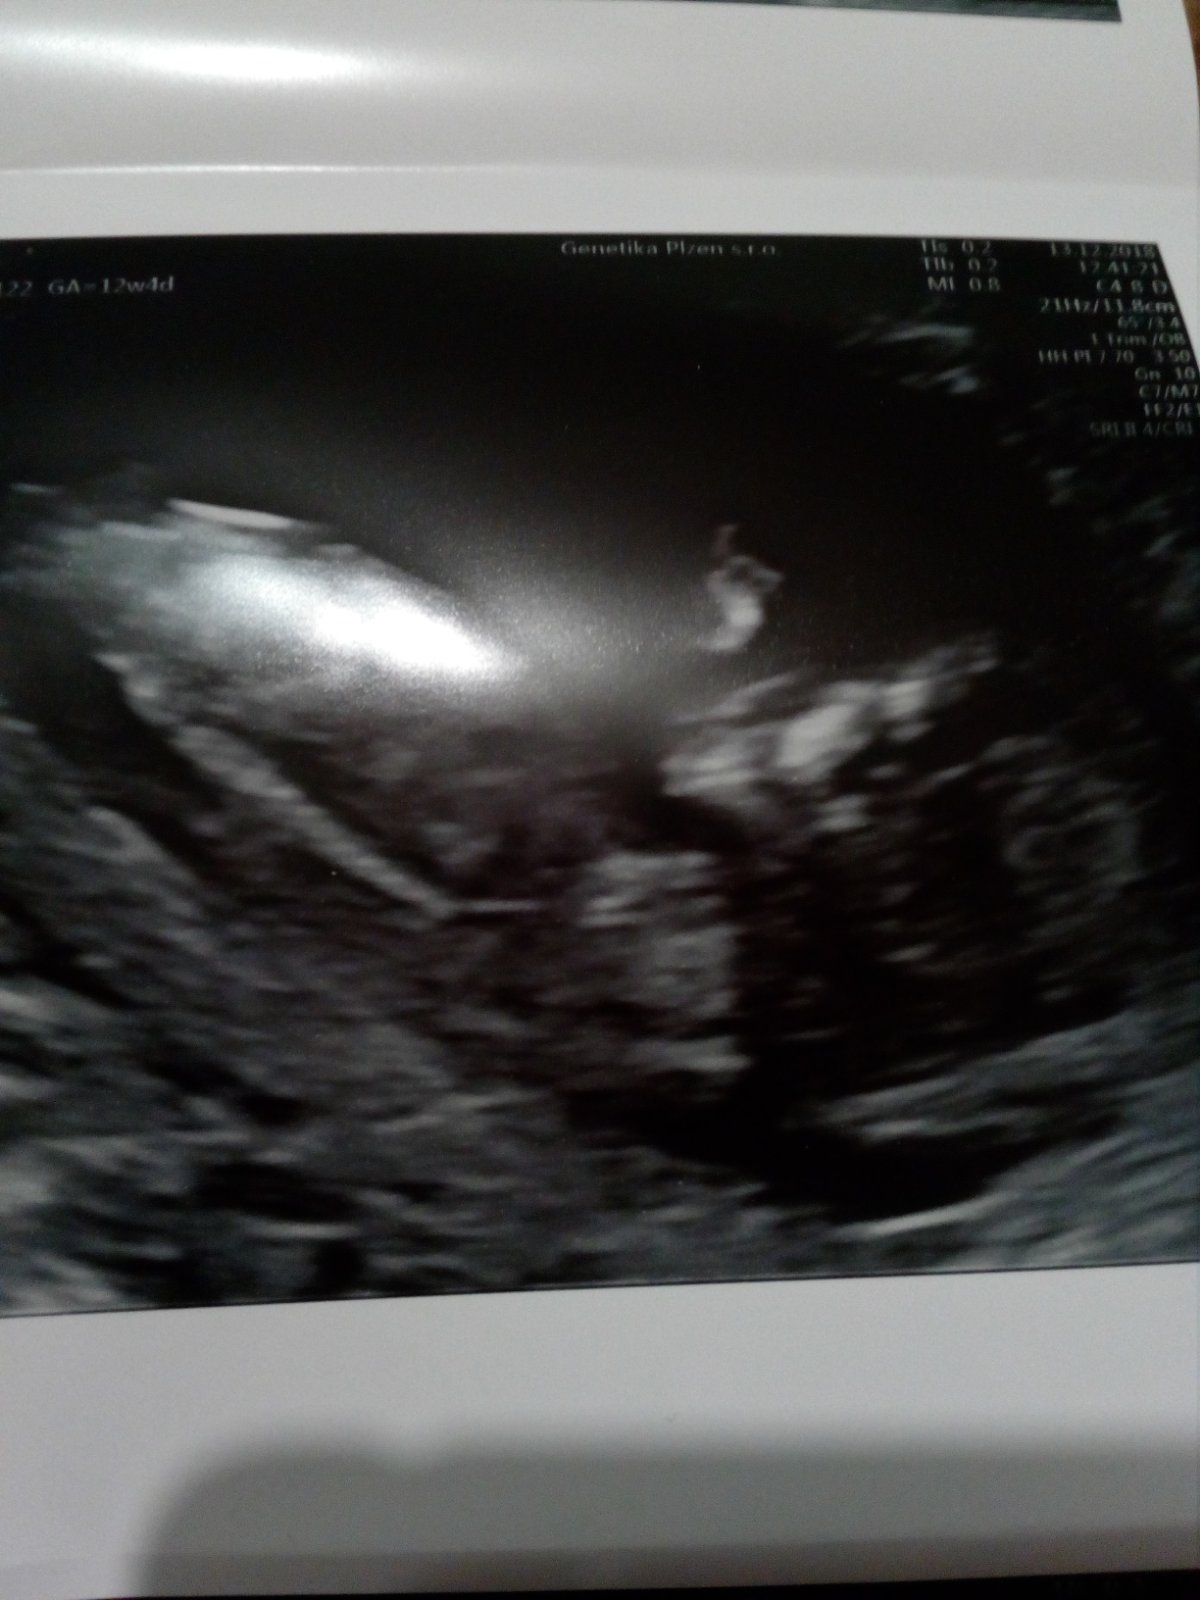

To nase dite dela "Zagorku". Porad se na screeningu vrtel a otacel na bok, byl zaboreny az dole. Ale asi nam hrozi prstickem😂vsimnete si toho?😊Jinak odpovidame 12+4 a termin porodu nam nezmenil. Rikali, ze pokud dnes nikdo volat nebude tak jsou vysledky krve dobre a nikdo nevolal takze super, spadl mi kamen ze srdce. Akorat mam nejake varixy tak mozna budu muset po porodu pouzivat heparin, ale nic vazneho to neni, ale zkoumal to podrobne.

autor@agatka2016 mohli jsme vedet co to bude, ale lezelo sikmo takze to neslo poznat. Doktor rikal, ze kdyby bylo hezky natocene tak by to mohl poznat.